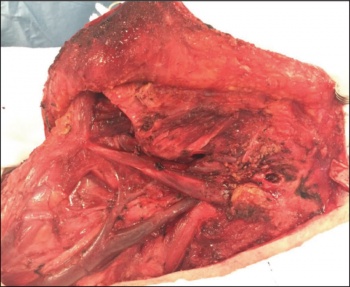

Figures 3 and 4. High grade cutaneous SCC with dissemination and into parotid and cervical lymphatics

Figures 3 and 4. High grade cutaneous SCC with dissemination and into parotid and cervical lymphatics(click to enlarge)